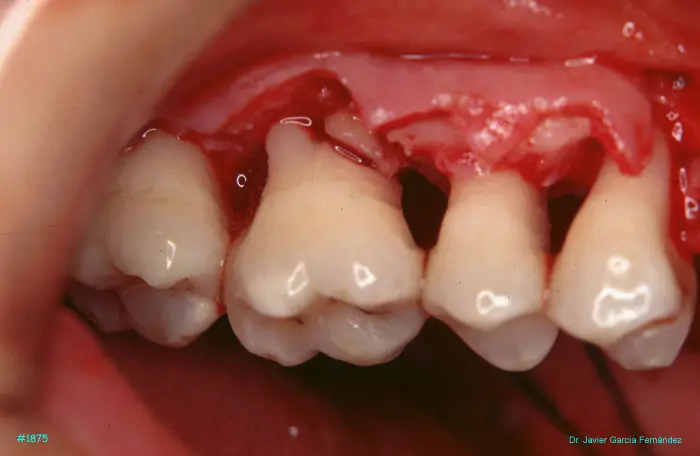

image 26